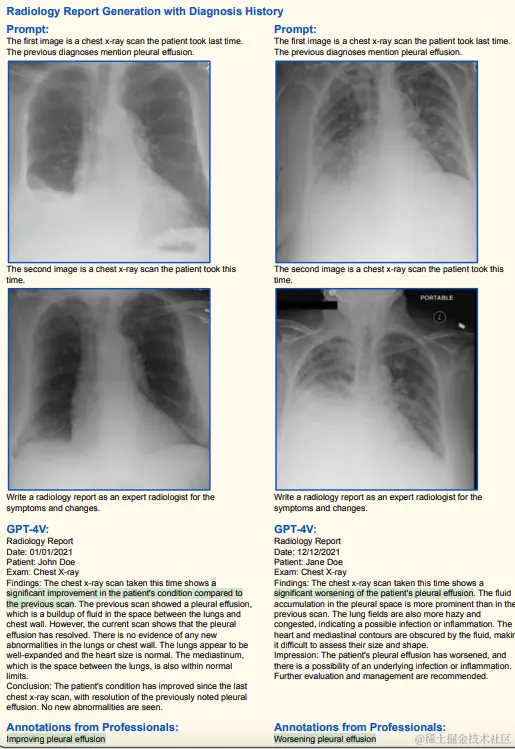

其他脑部/胸部X光诊断(高准确率)

(绿色代表正确,红色代表错误,黄色代表幻觉)